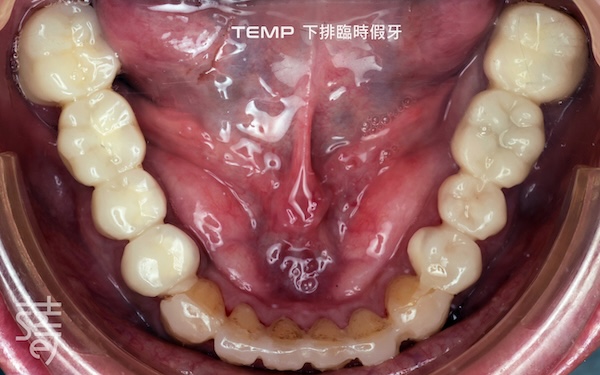

第三階段:全口美學重建 Stage Three: Full-Mouth Aesthetic Restoration

最後進行全口假牙與美學修復。許多人以為這一步只是追求美觀,其實這正是確保牙齒能長期穩定的關鍵步驟,讓美觀與功能同時回歸理想。

Finally, full-mouth prosthetics and aesthetic restoration were completed. Many assume this step is purely cosmetic, but it’s actually crucial for long-term stability.

🔼 蒔美引進 DSD 微笑設計系統,讓患者在假牙製作前預覽未來笑容樣貌。再由數位牙體技術師同步製作臨時假牙,讓患者在實際試戴過程中,提前感受理想笑容的美觀與舒適,並根據李先生主觀感受進行微調,找到最終的完美方案。

Smile Introduces the DSD Smile Design System, Letting Patients Preview Their Future Smile. Digital dental technicians then create temporary prosthetics, allowing patients to trial their ideal smile and comfort. Adjustments are made based on Mr. Li’s feedback to achieve the final, perfected result.